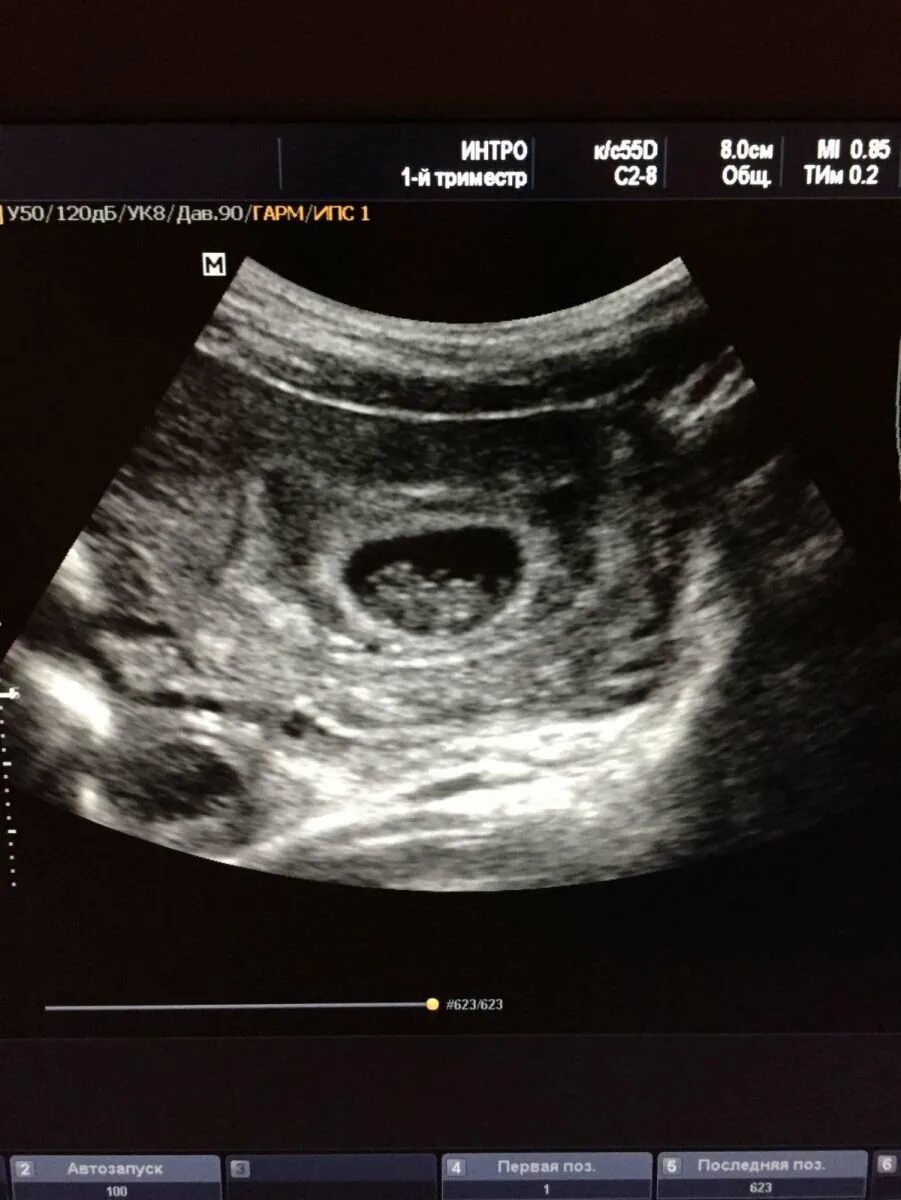

Как выглядит ребенок в 8 недель